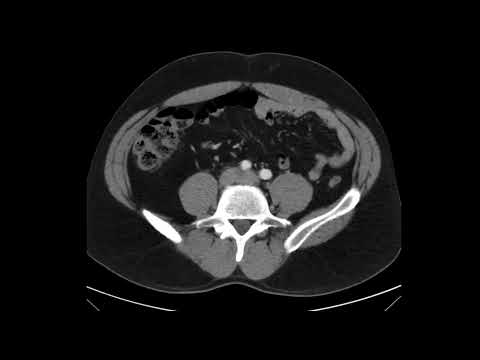

Massive Traumatic Retroperitoneal Hematoma, CT Unannotated